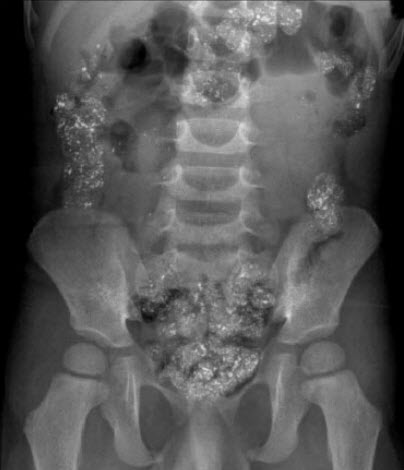

Jacob J. Rosenberg, MD; Sandra Lipovaca, MD; Dominick Sabatino, MD; Sujatha Kosuri, MD

A 3-year-old boy with a history of pica presented for a well-child checkup. He had missed numerous checkups, and his immunizations were delayed. His development was appropriate for age.